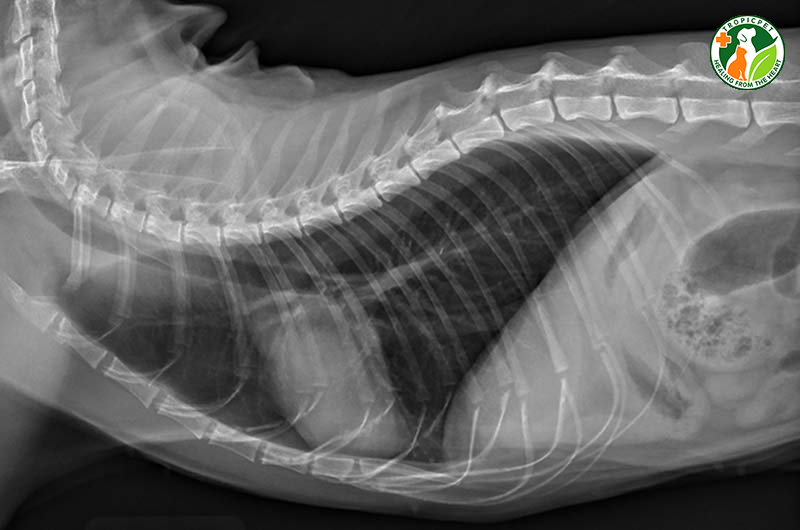

Khi mèo của bạn có dấu hiệu bị bệnh, việc chụp X-quang có thể là một bước đi cần thiết. Đây là một công cụ chẩn đoán quan trọng giúp bác sĩ thú y xác định những vấn đề nghiêm trọng như gãy xương, sự hiện diện của dị vật trong cơ thể hoặc các bệnh lý liên quan đến hô hấp. Nếu mèo bạn bị khó thở, chụp X-quang có thể giúp phát hiện ra nguyên nhân phát sinh những triệu chứng đó, chẳng hạn như bệnh tim hay tình trạng phổi.

Chụp X-quang cho mèo là một bước quan trọng trong việc chẩn đoán các vấn đề về sức khỏe, đặc biệt là khi nghi ngờ có gãy xương hoặc chấn thương. Quy trình này giúp bác sĩ thú y đánh giá tình trạng cơ xương và khớp của thú cưng, từ đó đưa ra những quyết định điều trị chính xác.

Trong quá trình chụp X-quang, mèo sẽ được đặt trên bàn chụp, ở một vị trí nhất định để đảm bảo hình ảnh rõ ràng nhất. Để có được hình ảnh chất lượng cao, bác sĩ thường sử dụng công nghệ chụp X-quang kỹ thuật số. Điều này không chỉ giúp đạt độ phân giải tốt mà còn giảm thiểu thời gian chờ đợi cho chủ nuôi.

Trong một số trường hợp, như khi mèo nuốt phải dị vật, bác sĩ có thể yêu cầu chụp X-quang với chất cản quang để quan sát đường tiêu hóa. Thăm khám lâm sàng toàn diện trước khi chụp cũng là một bước cần thiết để xác định chính xác những vấn đề mà thú cưng đang gặp phải. Tuy nhiên, để đảm bảo mèo không cử động trong quá trình chụp, thường cần phải sử dụng thuốc an thần hoặc gây mê.